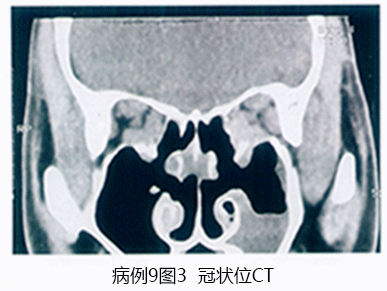

角膜地形图: 图9-3.

角膜地形图: 高度散光,角膜屈光力>48D

基于以上病史、眼部表现及辅助检查结果分析:双眼圆锥角膜(右眼急性圆锥)诊断明确。